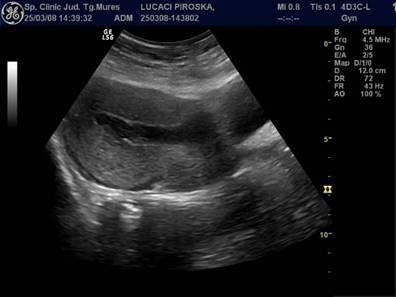

Fig. Nr. 332. Uterul postoperatie cezariana, ziua a IV a

Fig. Nr.333. Lauzie ziua a XII a postoperatie cezariana

Fig, nr.334 Lauzie ziua a II a dupa nastere spontana la termen, cavitate uterina cu minim continut

Fig. Nr 335 Lohiometrie in ziua a XXIII a postoperatie cezariana